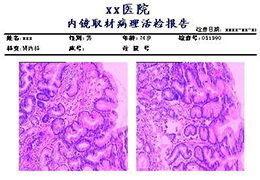

View X-Ray CT & MRI Scans Fast and Easily

Designed for surgeons, Pro Surgical 3D makes it easy to view patient scans quickly. Pro Surgical 3D facilitates the optimal 3D treatment and assessment workflows based on X-ray CT and MRI scans – and best of all, it’s FREE!

Everyone – including surgeons, patients and their loved ones – benefits from being better informed by the wealth of information buried within CT and MRI scans. Pro Surgical 3D gives surgeons more information to develop optimal treatment plans for patients. It also helps patients and their support group better understand their medical condition and proposed treatment options.

Better understanding of a condition, disease or diagnosis

Ability to clearly see the condition or disease